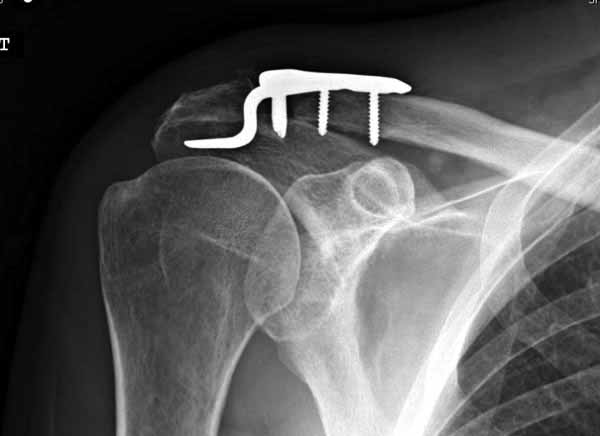

1.JPG

60KB (62415 bytes)

|

Отправитель: Серж 24 Июнь 2011, 13:41

foto

2.JPG

12KB (12589 bytes)

Re: ключичная пластинка

Отправитель: Серж 24 Июнь 2011, 13:42

foto 3

3.JPG

14KB (15209 bytes)

Отправитель: Серж 24 Июнь 2011, 13:43

foto 4

4.JPG

14KB (14434 bytes)

Отправитель: Серж 24 Июнь 2011, 13:45

foto 5

коллаж у меня не получился, пришлось отдельно рентгенограммы присоединить :-))

5.JPG

15KB (16356 bytes)

Замечание понял, спасибо и нормальные рентгенограммы, молодец!

Во вторых, это хорошо что нашли длинную пластину, я об этом писал "пластина короткая, не покрывает медиальный диафизарный фрагмент ключицы", и у нас не получилось, пластина не выдержала...

Мне кажется что если понять принципы, то можно использовать и короткую пластину. Что мы с успехом применяли раньше и применяем сейчас, но уже более осознанно. В вашем случае Серж, у меня стойкое ощущение, что необходима дополнительная иммобилизация, так как неправильно выбрано место введения крючка и при ранней нагрузке пластину просто вырвет. Если вам несложно не могли бы вы продемонстрировать прямую и боковую проекцию и в более хорошем качестве. ИМХО

Теоретически можно использовать и короткую пластину. Но на операции дистальный отломок( акромиальный конец ключицы ) был коротким и оскольчатым, поэтому крючок и использование там блокированных винтов в пластине было очень уместно. Доступ - "сабельный удар". Точка введения крючка - сразу сзади от ключично-акромиального сустава. Если честно - больше внимания уделяли репозиции отломков и адекватному расположению пластины на ключице :-) крючок проверяли на прочность фиксации за акромион и полный объем движений в плечевом суставе. После операции рука на косынке, нагрузку ограничили. Снимки есть в нормальном разрешении, но здесь "размер файла не превышал 75 кб." Если есть необходимость залью в пикассу...